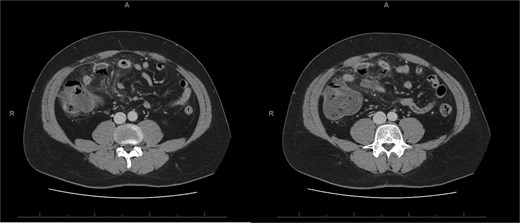

A 45-year-old male presenting with a 10-day history of isolated right lower quadrant (RLQ) abdominal pain. His history included deep vein thrombosis, coronary artery disease with prior STEMI, left anterior descending artery stenting in 2014, and ongoing antiplatelet therapy with aspirin. Upon admission, RLG tenderness was noted. Laboratory revealed leucocytosis (WBC 16 G/L) and elevated CRP (70 mg/L). E-CT revealed superior mesenteric and portal systems thrombosis with ischemia of a small bowel loop in the RLQ, characterized by absent bowel wall enhancement and free fluid (Fig. 4). Besides these findings, he was managed conservatively with a UFH bolus of 5000 U/l, followed by a continuous infusion of 36 000 U/l over 24 h (target INR 0. 35–0. 7), Ceftriaxone and Metronidazole, bowel rest, and ICU monitoring for 48 h. Clinical and biological improvement was rapid. E-CT on the second day showed no signs of perforation (Fig. 5). He was discharged after 7 days on LMWH (enoxaparin sodium 90 mg every 12 h). Twenty days later, he re-presented with acute RLQ pain and localized peritonism. E-CT revealed a covered perforation of the previously ischemic small bowel loop (Fig. 6). A segmental bowel resection with primary anastomosis was performed by laparotomy (Fig. 7). The postoperative course was uneventful, and he was discharged on postoperative day 4 with sodium enoxaparin 90 mg/12 h.

E-CT in the second patient at admission. White arrows showing porto-mesenteric thrombosis. Dashed arrows indicate a portion of small bowel loop ischemia in the right lower quadrant characterized by the absence of bowel wall enhancement and free fluid.